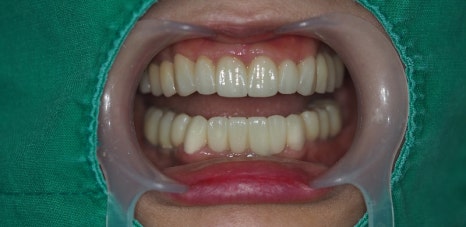

최종 치료 완료된 구강 모습입니다. 앞전의 구강 사진과 비교해보시면 자연스러운 치아의 모습이 완성된것을 확인 할수 있습니다.

전체 최종 치료 기간은 9개월 소요 되었습니다

환자분은 사람들과 많이 대면하고 이야기 해야 하는 서비스 직이라 그때마다 불편하셨는데

지금은 너무 편하게 지내고 있기도 하고 치료과정과 결과도 너무 만족 스러워 하셔서

저희가 너무 뿌듯할 따름입니다.